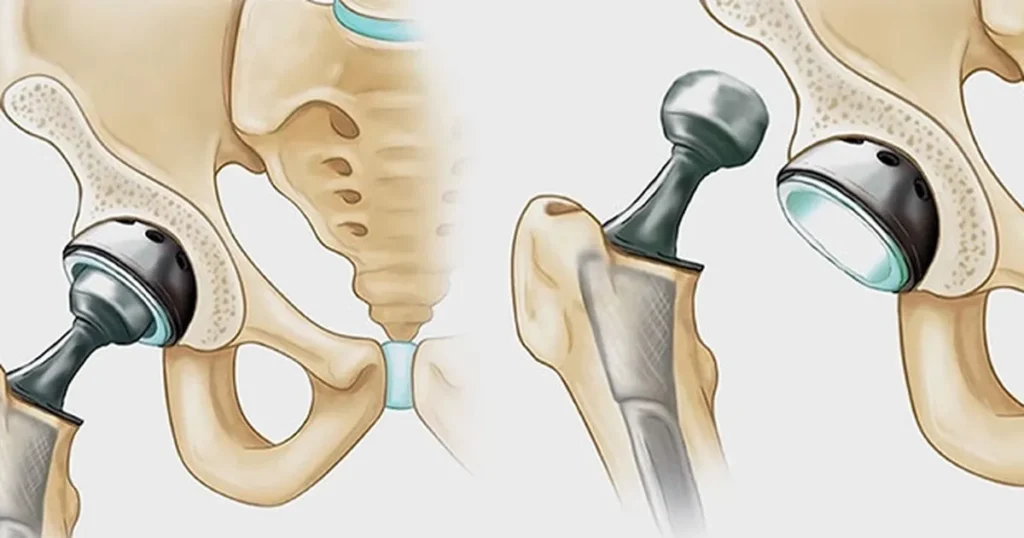

Kalça Protezi Nedir?

Kalça protezi, hasar görmüş eklem yüzeylerinin çıkarılarak yerine metal, seramik veya yüksek dayanımlı plastikten yapılmış yapay eklem yüzeylerinin yerleştirilmesi işlemidir. Amaç; ağrıyı ortadan kaldırmak, hareket kabiliyetini geri kazandırmak ve yaşam kalitesini artırmaktır.